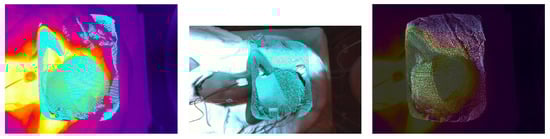

3.3. Fusion Dataset

3.3.1. RetinaNet

3.3.2. YOLOv3

4.1. Comparison of Theoretical Approach for the Sensor Fusion